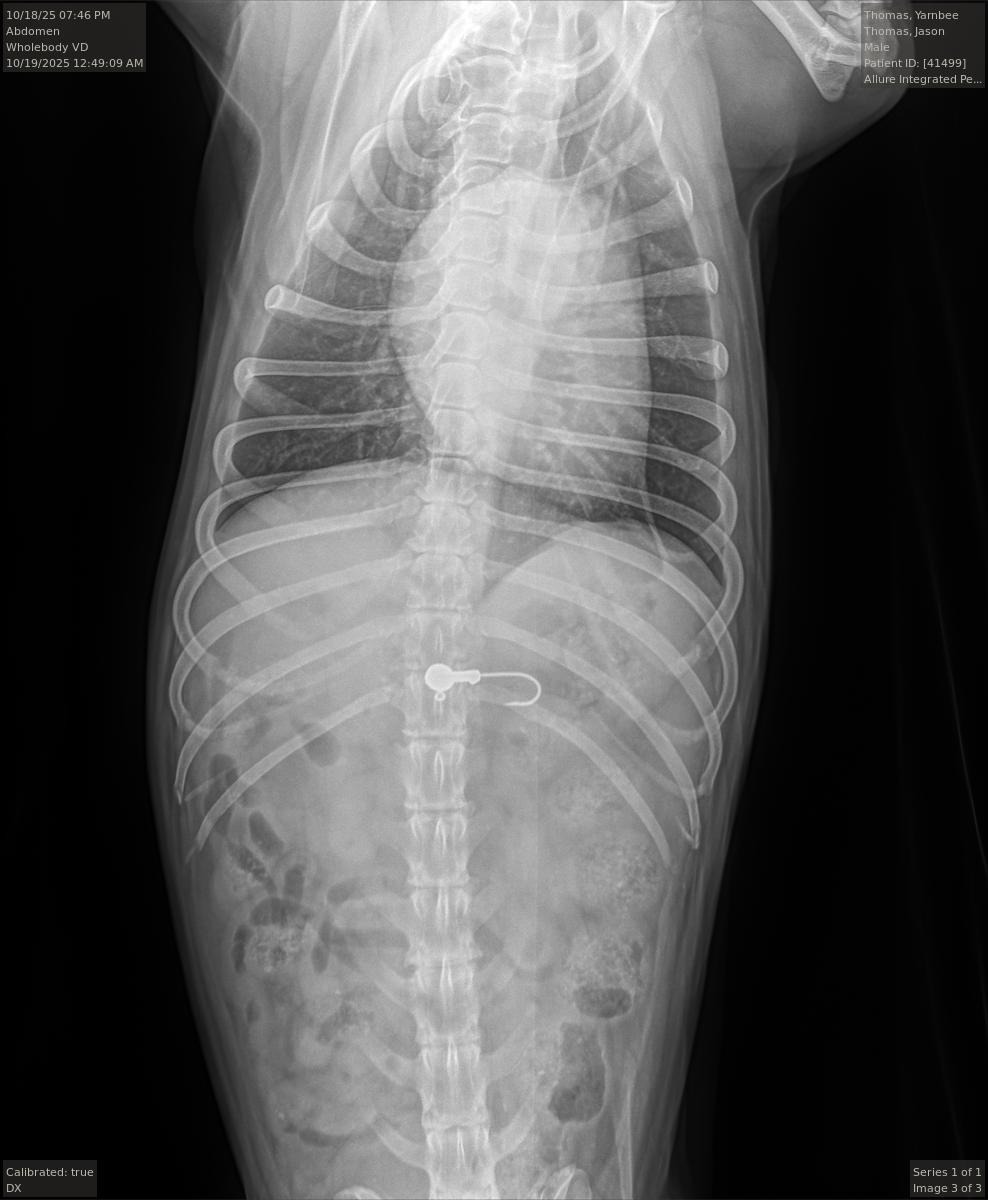

My psychiatric service dog Yarnbi swallowed a fishhook at the river when a kid put his baited pole down. There was a chance it could pass, but also that it could shred his guts on the way out. This is a total freak situation. I do healing bodywork at festivals, which have been slow as of late and cannot afford the cost of this surgery. I can reciprocate bodywork sessions (more at the end on that note).